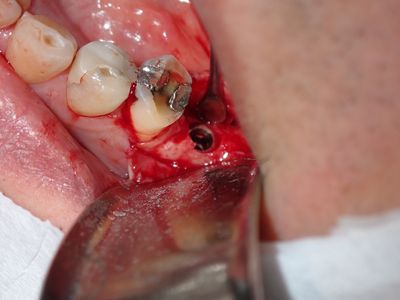

WYu - 36 implant

Loss of lingual bone, osteotomy prepared in ideal position, prepared to about 2.8mm, remainder with combination of densah drills for crestal 1/2 and straumann drills to length. Implant placed with ample bone around it.